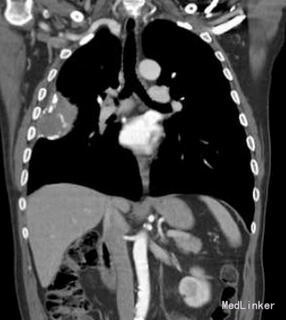

患者:男性,68 岁,出现咯血、胸痛,偶有发冷;无发热、体重减轻和呼吸困难。该患者童年有结核病病史,未接受抗结核治疗,后右下胸膜出现胸膜钙化且保持稳定。

胸部 CT 显示右下肺后段胸膜处有一 5.5x4.5cm 不透明的低密度影和多个非钙化肺结节(直径≤4 毫米)及纤维条索和隆突下淋巴结钙化。